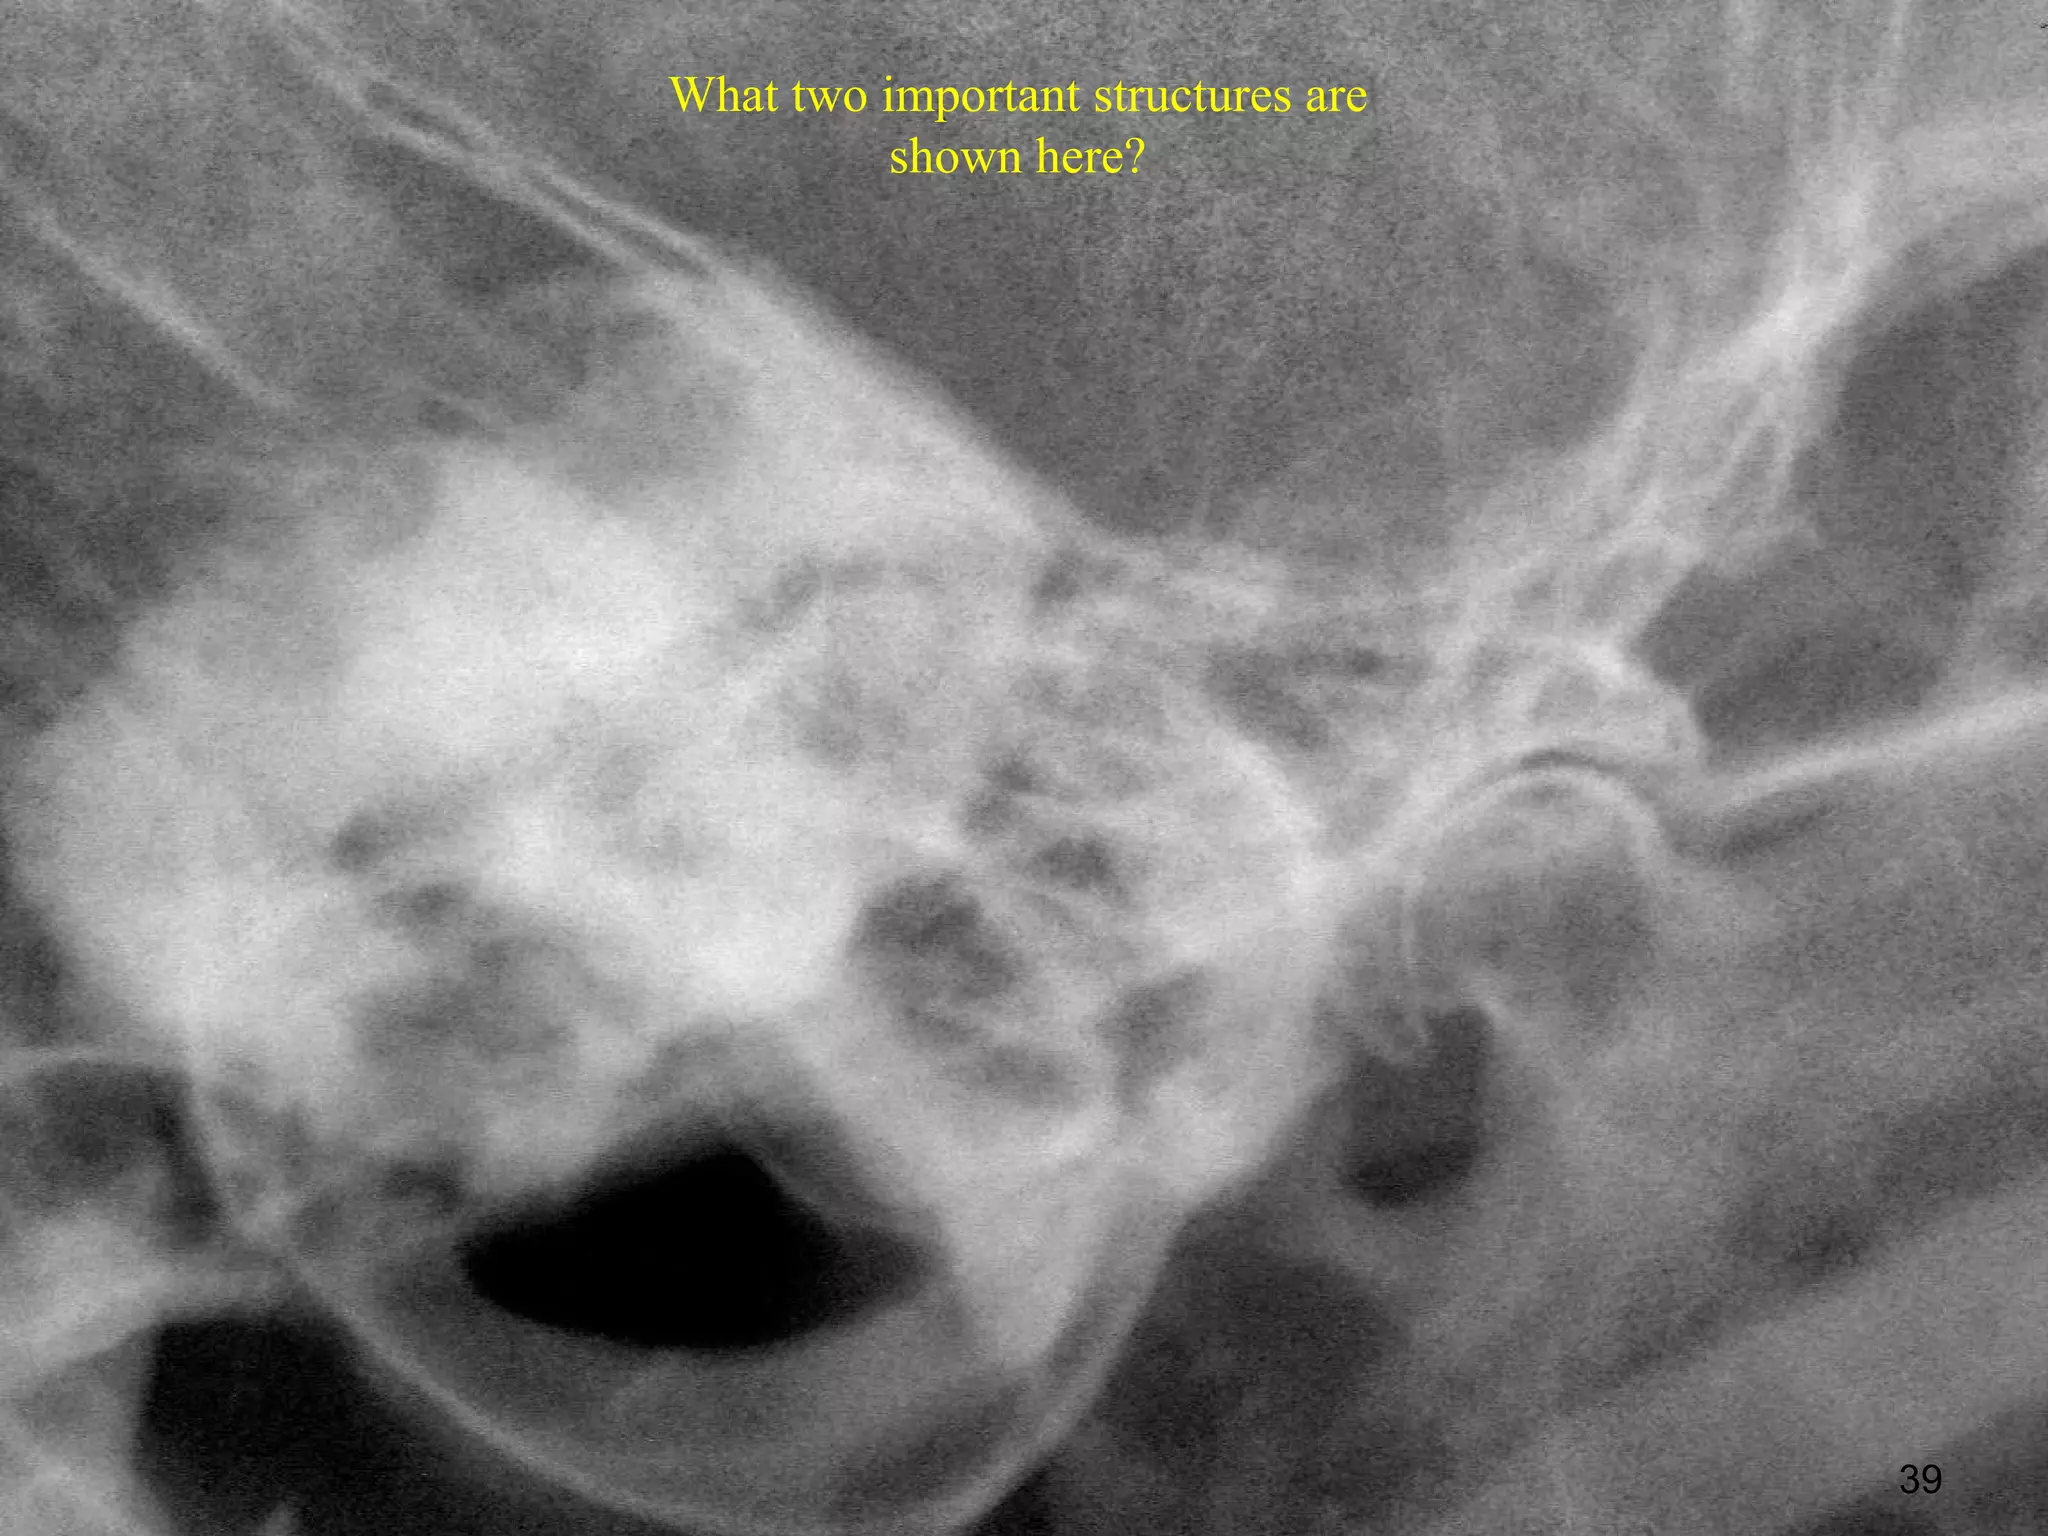

What two important structures are

shown here?

39

What two importantstructures are shown here? 39